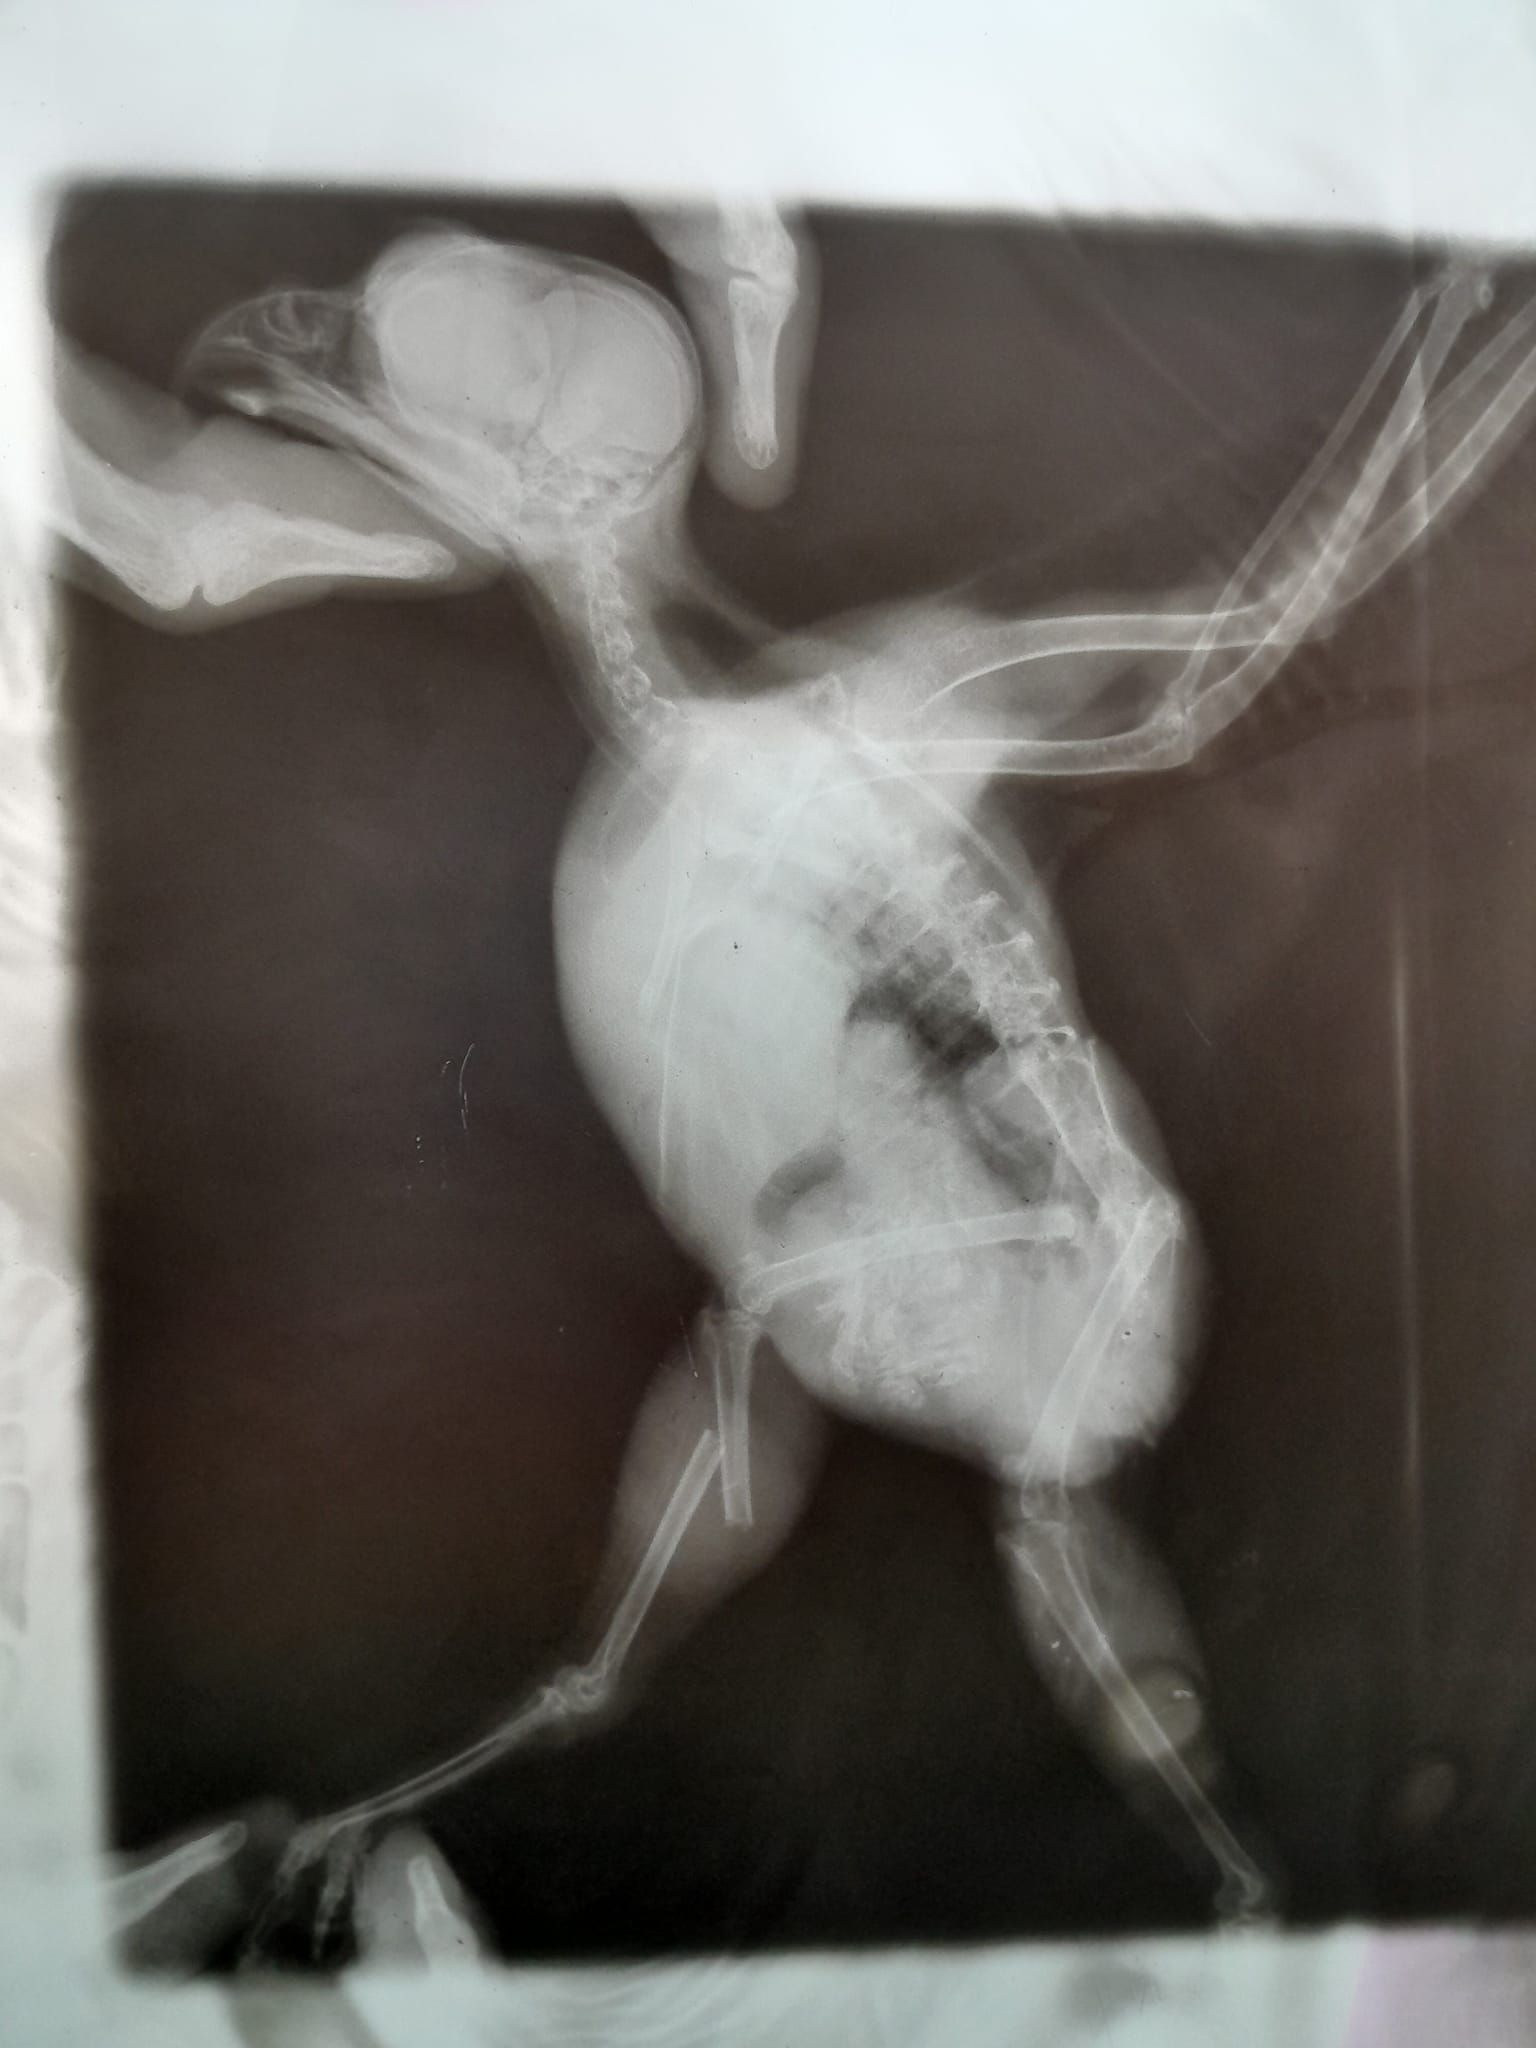

Украинские бойцы передали ей боевого сыча Джонни, которого они обнаружили на Авдеевском направлении. Птица получила сильный ушиб с правой стороны, у нее диагностировали черепно-мозговую травму, переломы коракоида и правой голени, плюс значительное воспаление в желудочно-кишечном тракте.

Пока стабилизирую и буду договариваться об операции, но не раньше чем через 5-6 дней. Птица однозначно ПМЖ, – отметила волонтер.